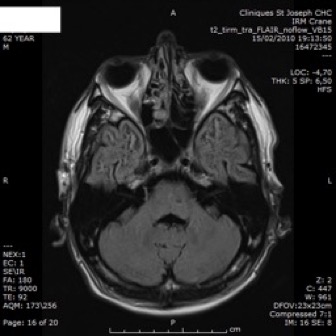

IRM

- anomalies de la substance blanche: LEP

- infarctus de petite taille, souvent profonds: sous-corticaux.